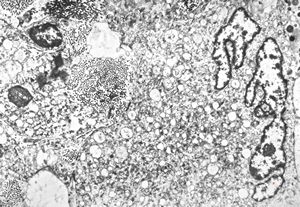

brain vessel - CADASIL - arrows:granular osmiophilic material (GOM)between basement membranes

brain vessel - CADASIL - arrow:granular osmiophilic material (GOM)in basement membrane